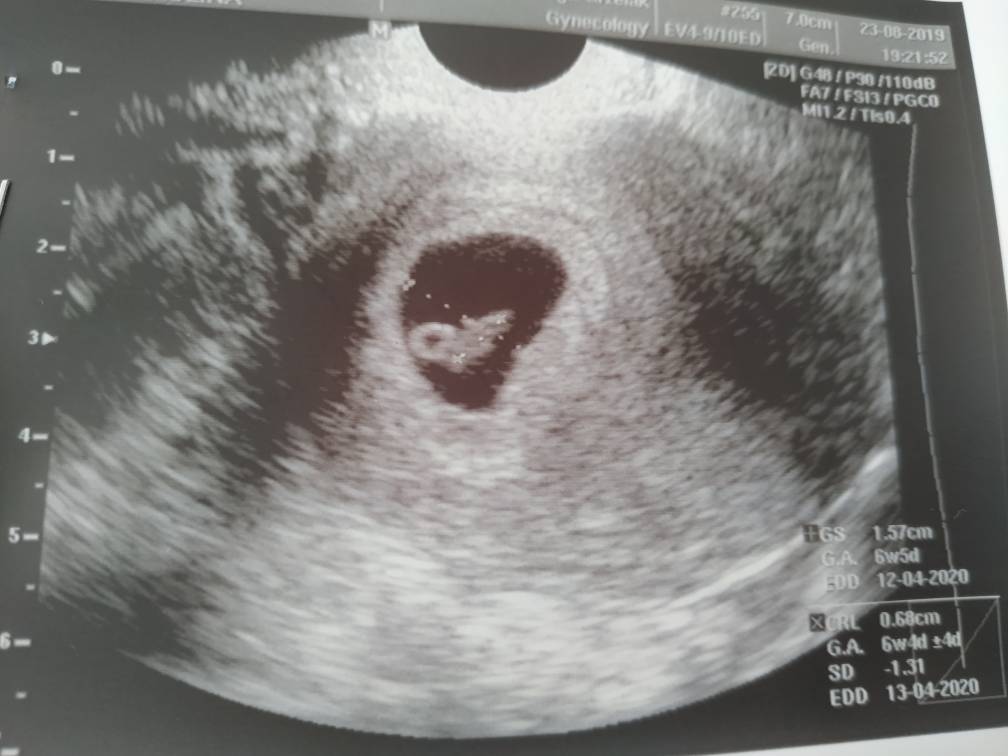

To jeszcze raz ja... Na szybko ogarnęłam lekarza, ale i tak musiałam zapłacić. Wszystko w porządku. Fasolka rośnie. Nie ma krwawienia żadnego, nic nie stwierdziła. Akcja serca jest jak trzeba. TP - 12.04.2020Zobacz załącznik 1013320

Dziewczynki jest jedna dzidzia, 1.78cm, tetno 180, :)